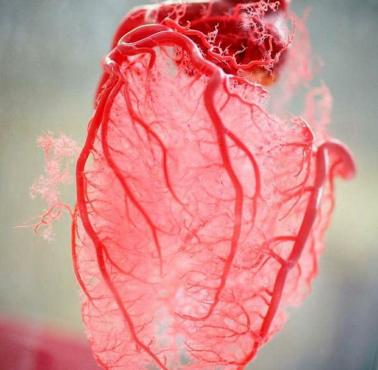

Układ nerwowy człowieka. Na zdjęciu widać m.in. mózg, rdzeń kręgowy, nerwy rdzeniowe i splot lędźwiowy